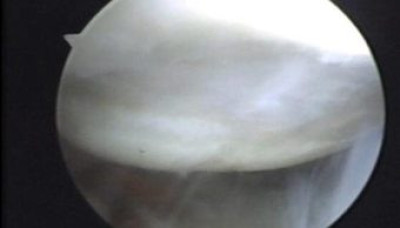

Durante la artroscopía se comprueba la existencia de la lesión de Hill Sacks, la cual es una lesión osteocondral por las luxaciones anteriores que ha sufrido el paciente